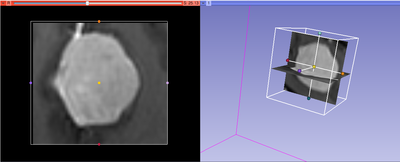

This module allows to extract rectangular subvolume from a scalar image, with the subvolume defined by Slicer ROI widget.

- Interpolated cropping will resample the content of the image within the ROI given the interpolation options explained below. If disabled, then only the extent of the volume is changed but spacing and axes directions remain exactly the same.

- Volume information shows preview of spacing and dimensions of the cropped output volume and, for comparison, the input volume. Average dimensions of a volume is about 200-300 voxels along each axis. If the resolution is increased using Spacing scale and Isotropic spacing then it is recommended to reduce the region of interest so that the dimensions are not increased significantly.